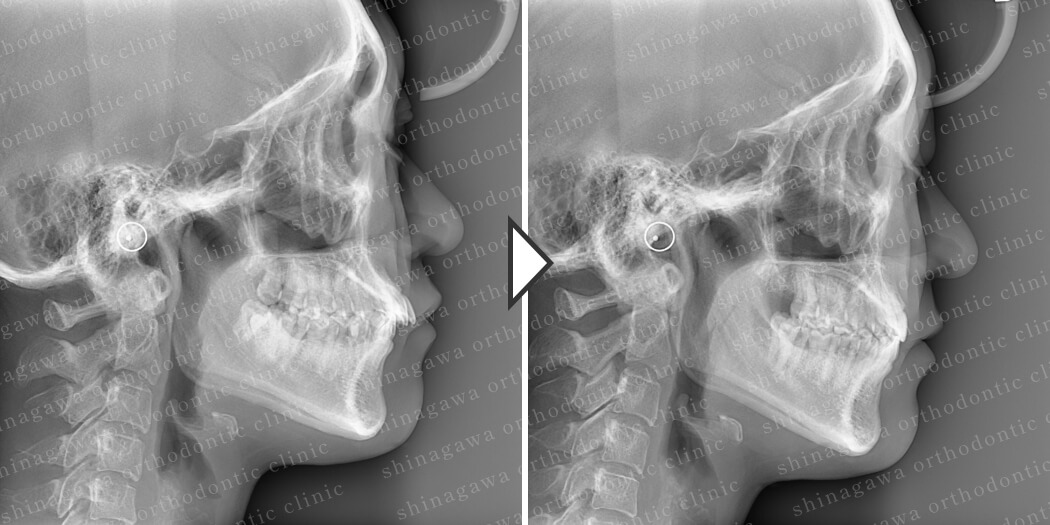

症例3

下顎前突

| 年齢 | 34 歳 |

|---|---|

| 性別 | 女性 |

| 住所 | 東京都目黒区 |

| 主訴 | 出っ歯 |

| 不正咬合の種類(診断) | 下顎前突 |

| 装置 | 表ワイヤー |

| 抜歯/非抜歯 | UR4, UL4 |

| 期間 | 24M |

| 費用 | 935,000 円 |

| リスク・副作用 | 矯正治療による歯の移動に伴う痛み, 虫歯, 歯肉退縮, 歯根吸収 |